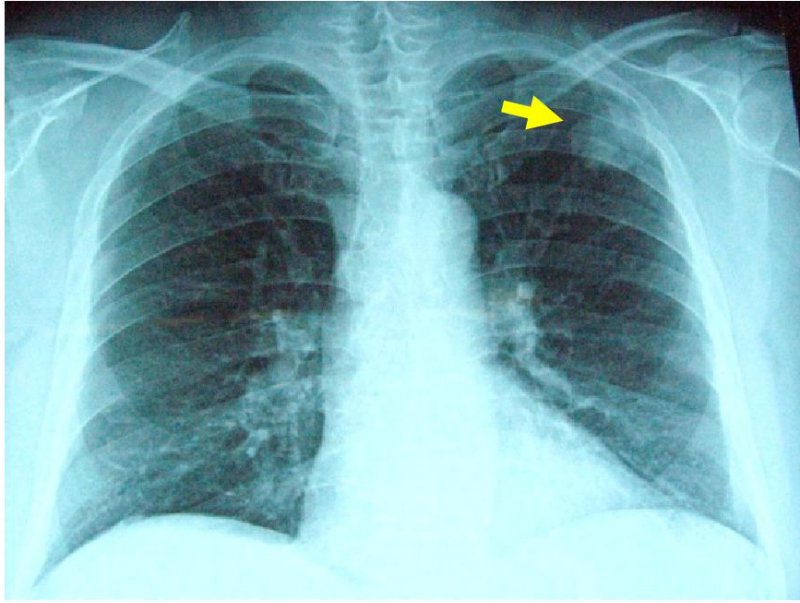

左肺癌の画像所見

胸部XP(左上肺野に腫瘤影あり)

胸部CT